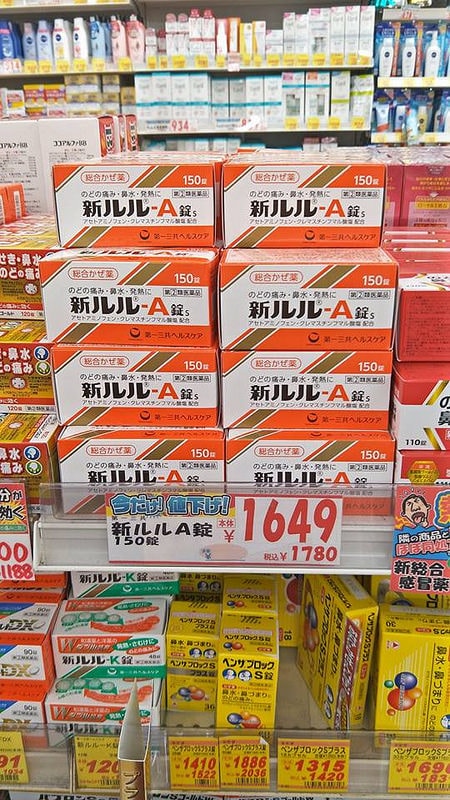

比起新LULU A

我媽更愛這一款葛根湯的顆粒